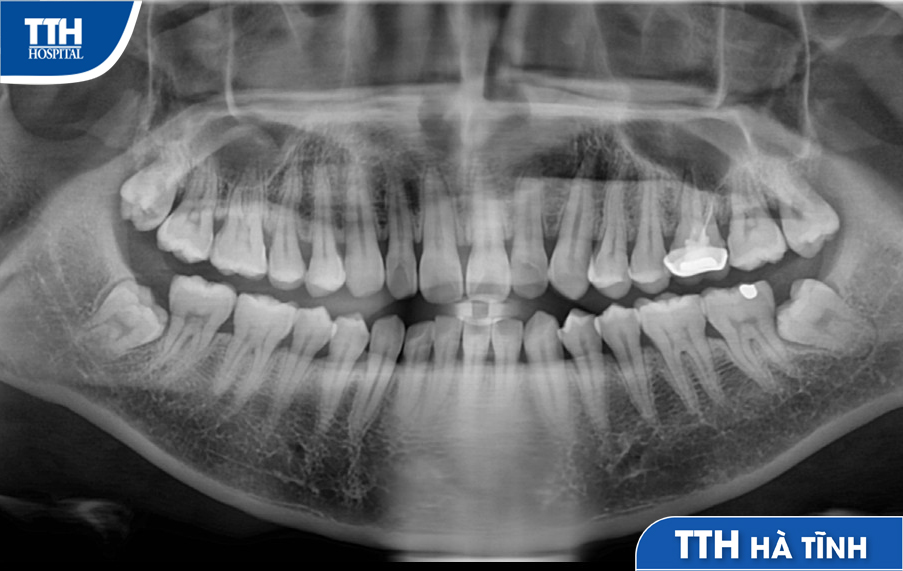

✔️ Bước 2: Thực hiện các xét nghiệm cần thiết để đảm bảo an toàn và tiến hành chụp X-Quang để xác định vị trí và thế mọc chân răng. Đây là bước quan trọng để bác sĩ xác định phương pháp nhổ răng an toàn và phù hợp.